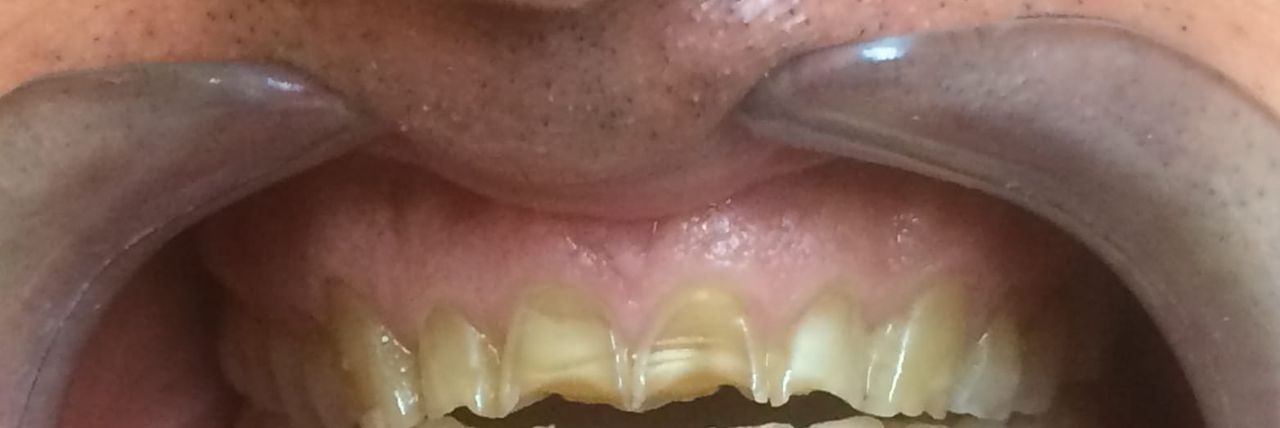

Foto e video

• Studio Dentistico LUCA STRAZIOSO terapia parodontale  •